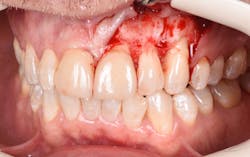

Figure 17: Patient presented with buccal vestibule swelling and complaining of pain. Swelling is visible and palpable with discoloration of the soft tissue.

Figure 18: Pre-op radiograph shows retrograde peri-implantitis possibly from previous periapical pathology.

Figure 19: Immediately after incisions and raising a full-thickness flap, suppuration was noted on the apex area of the implant.

Figure 20: An osteotomy was done to access apical area of implant No. 8 utilizing the Er:YAG laser at 20 pps/70 mJ. The then-exposed area was irradiated using a combination of detoxification and biostimulation of the bone and implant to prepare the area to receive a bone graft.

Figure 21: After mechanical debridement and surface detoxification